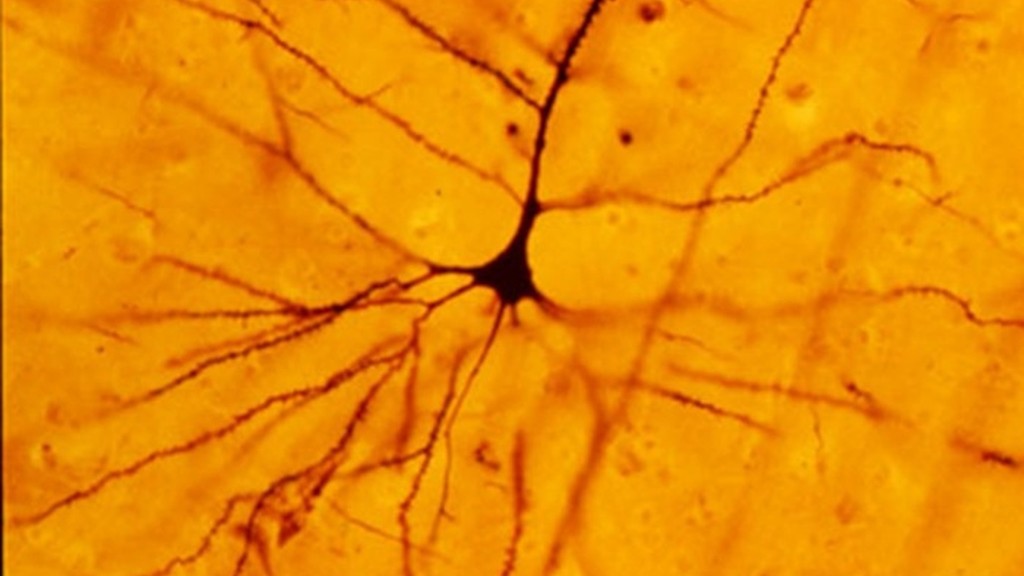

Dalla scoperta dei cosiddetti neuroni specchio , che si attivano sia quando compiamo un'azione sia quando la osserviamo fare a qualcun altro, agli studi che hanno fatto luce sulla malattia di Huntington , un raro disturbo genetico neurodegenerativo per il quale si stanno ora sperimentando possibili terapie. Tanti degli sviluppi compiuti oggi nel campo delle neuroscienze rappresentano l' eredità di Camillo Golgi e della sua ' reazione nera ': la tecnica di colorazione da lui sviluppata nel 1873 , che permise per la prima volta di evidenziare e osservare le singole cellule cerebrali .